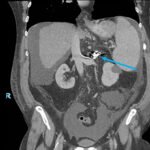

Endovascular coil embolization continues to become a more frequent modality of addressing hemorrhage and bleeding in patients. Migration refers to the coil unraveling or moving from the original embolization site. Migration of a coil is a known complication which can lead to serious consequences based on where the coil migrates. Despite increasing efforts to improve safety and technique, the risk of migration remains. We present a case of an embolization coil that migrated to the right ventricle, which was incidentally found roughly 2 months after undergoing an interventional radiology procedure for gastric variceal bleeding. The patient presented to the emergency department with dyspnea and abdominal pain. Unique images were obtained during his visit and in subsequent follow-up. As use of vascular embolization coils continues to become more commonplace, understanding the risks and complications of these procedures remains an important aspect of providing care for patients once they have left the interventional radiology suite. Coil migration should be a differential to consider in patients who present to the emergency department with signs or symptoms of arrhythmia or pulmonary embolism who have undergone a coil embolization procedure.